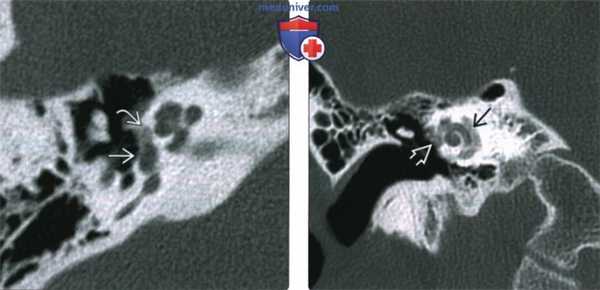

(Слева) При аксиальной КТ правой височной кости у молодого взрослого с прогрессирующей кондуктивной тугоухостью визуализируется типичная отоспонгиозная бляшка (фенестральный отосклероз) спереди от овального окна в области предполагаемой локализации щели перед окном.

(Справа) При корональной КТ правой височной кости у пациента со смешанной тугоухостью визуализируется рентгенонегативное «гало» вокруг улитки, обусловленное кохлеарным отосклерозом. Обратите также внимание на сопутствующий фенестральный отосклероз.

2. КТ при отосклерозе:

о Ранние изменения на КТ височных костей:

- Первичные изменения: рентгенонегативный фокус в области переднего края овального окна (ФОто)

- Поражение всех краев овального и круглого окон

- Возможно поражение слуховой капсулы внутреннего уха (КОто)

- Симптом двойного кольца или рентгенонегативное «гало», окружающее улитку, в случае тяжелого КОто

(Слева) При аксиальной КТ правой височной кости определяется бляшка смешанной структуры (со склеротическим и «прозрачным» компонентами) спереди от овального окна с вовлечением щели перед окном. Склеротическая часть бляшки при фенестральном отосклерозе обусловлена процессом заживления, рентгенопрозрачная часть - активным процессом.

(Справа) При аксиальной КТ левой височной кости визуализируется отоспонгиозная бляшка смешанной (склеротической и рентгено-негативной) структуры, приводящая к обструкции круглого окна. Отосклероз предрасполагает к невозможности протезирования стремечка и затрудняет кохлеарную имплантацию.